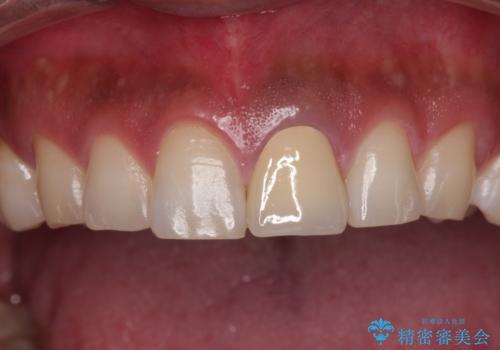

- 神経を取り除いたことで変色した前歯を気にして来院された患者様です。

根管治療はやり直さずに、ファイバーポストを使用した土台を植立してオールセラミッククラウンにて補綴することとしました。

神経を取り除いた歯は時間とともに変色してきます。

クリーニングやホワイトニングでは改善できないため、オールセラミッククラウンなどによる補綴治療が必要となります。